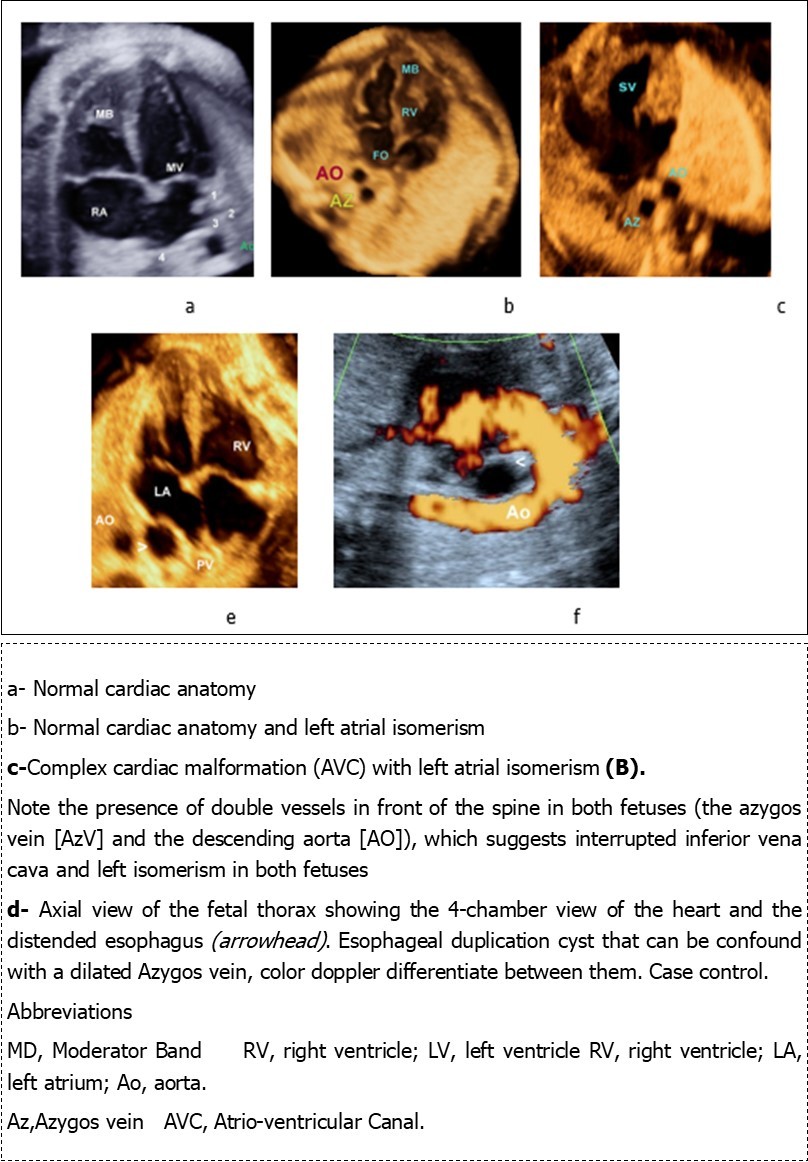

Figure 3.Four-chamber views in four fetuses:

Absence of the hepatic segment portion of the IVC with azygos continuation into the right or left SVC is referred to as an interrupted IVC and it have been reported as an incidental finding at autopsy as early as 1793 by Abernethy in a 10-month-old infant with polysplenia and dextrocardia. Moller et al 18 emphasized the association, 11 and now it is considered an excellent marker for the presence of left atrial isomerism. a finding that occurs in about 80%. Therefore, a careful examination of the IVC should be performed in the suspected heterotaxy patient. 24, 28. In this condition, the venous drainage from the lower extremities reaches the superior vena cava via the azygos vein (azygos continuation) or via the hemiazygos vein (hemiazygos continuation) emptying into either a right-sided superior vena cava or into a persistent left superior vena cava. It can be recognized by the observation of the aorta and the (dilated) azygos vein on its right or left side (hemiazygos) either in the upper abdomen or at the level of the four-chamber view 31. Sheley et al 29 described it as the ‘double-vessel sign’ (Figure 3) and found it in all eight fetuses with left isomerism that they examined, but also in one false-positive case with right isomerism. If the examiner is aware of this sign, he can easily detect it prenatally on real-time imaging and confirm it using color Doppler. Three of our patients presented this sign (Figure 3), care should be taken not to confound it with other conditions that mimic a ‘double-vessel sign’, for example, esophageal duplication cyst, that can be confound with a dilated azygos vein in 4 chamber view, color doppler can differentiate between the two conditions. (Figure 3 d, f).